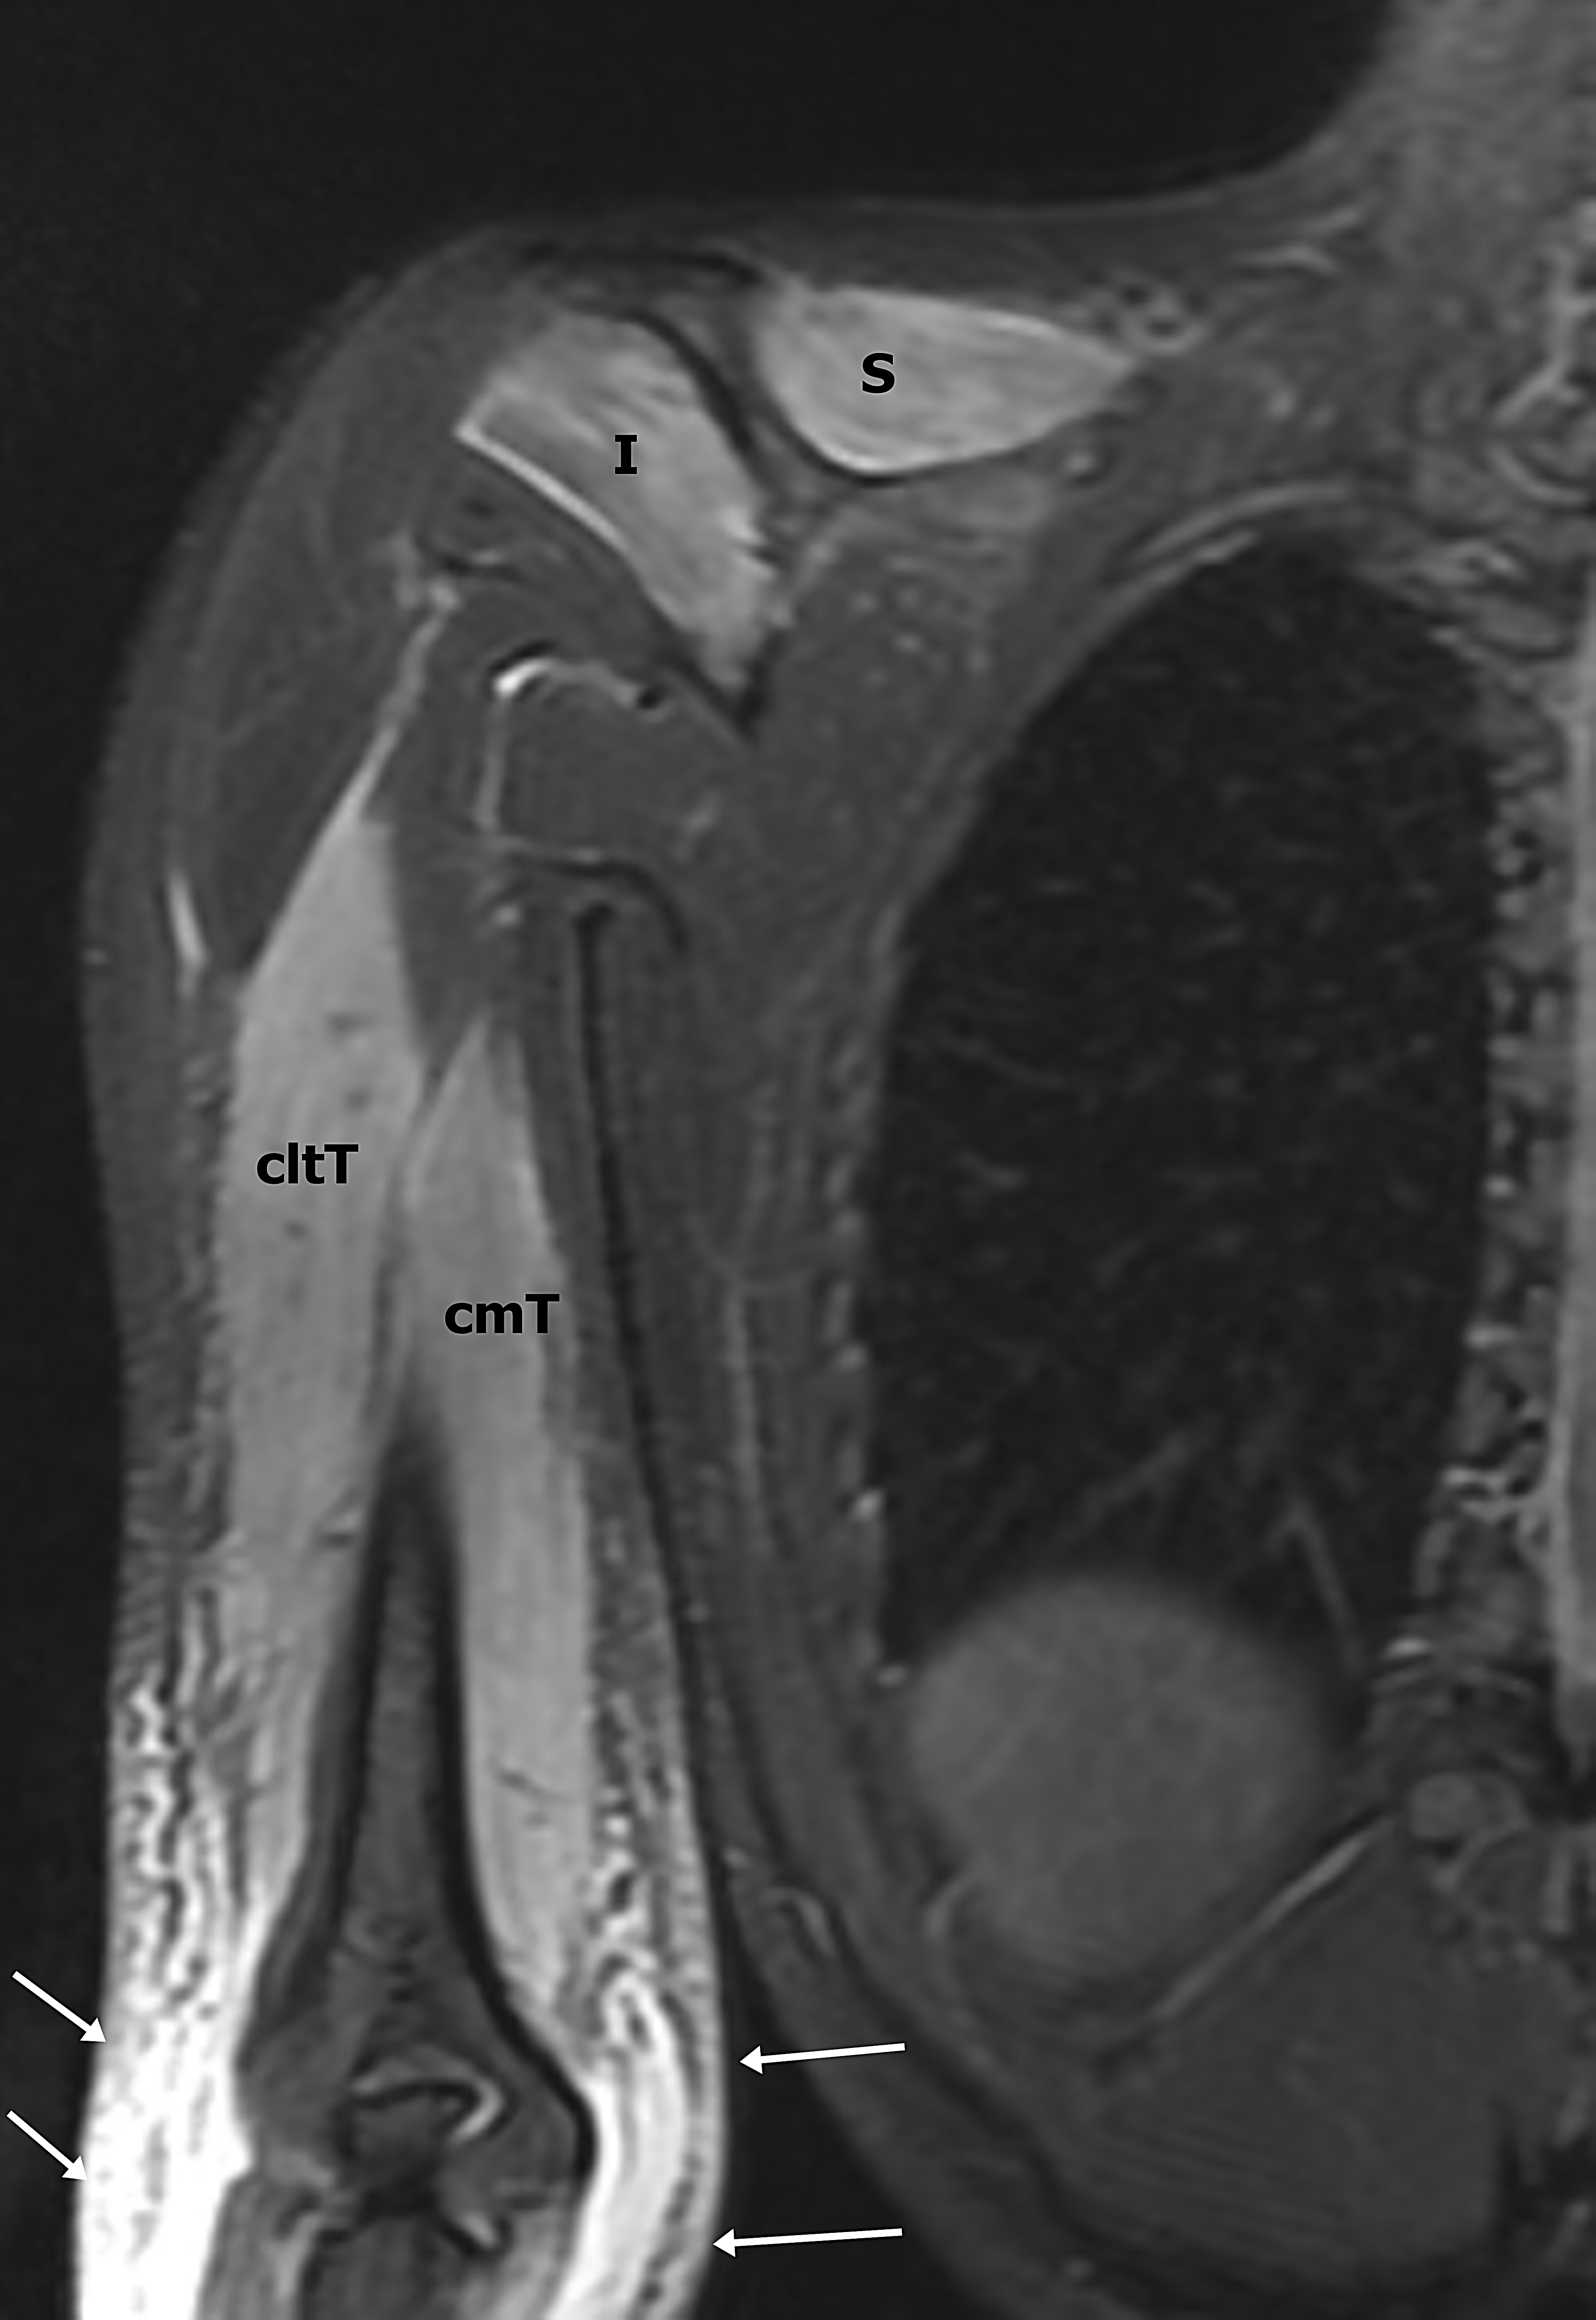

Presentación del casoMujer de 27 años de edad, con antecedentes de sepsis por estafilococo epidermidis, secundario a infección posquirúrgica de cirugía mamaria hace 3 meses, sin otros antecedentes de relevancia. Consulta en el departamento de urgencias, por presentar omalgia aguda, asociado a edema e impotencia funcional de hombro derecho, que comenzó 3 horas después de realizar actividad física intensa de CrossFit, consistente en movimientos de flexo-extensión de miembros superiores con peso.Descargas